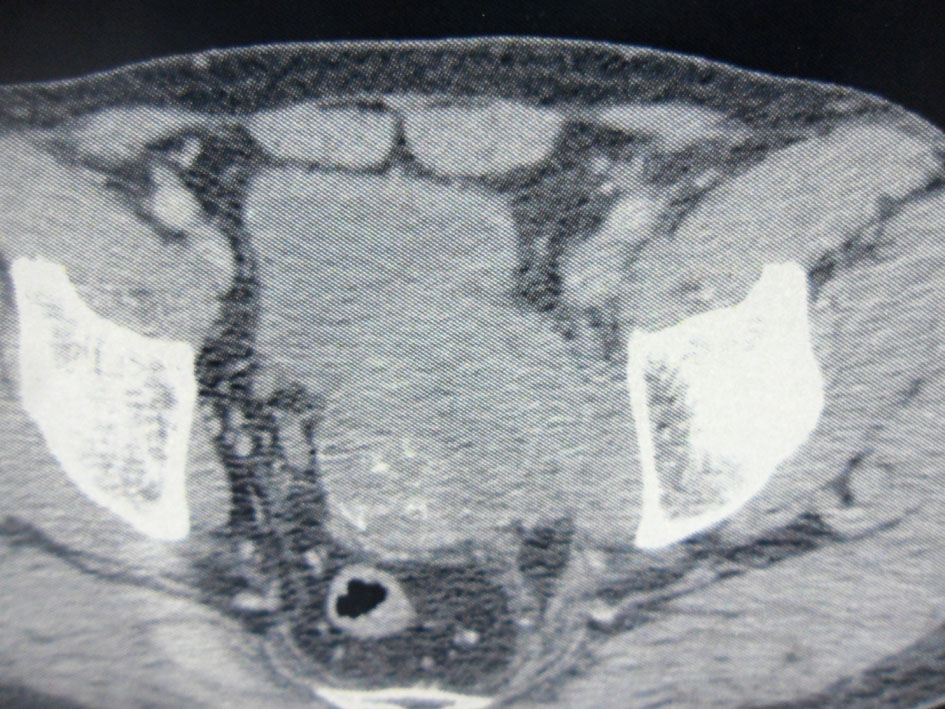

Computed tomography showed an 8.5 × 6 cm solid and heterogeneous mass on the left superior aspect of the prostate with cystic area and peripheral calcifications (Fig. 2).

![]() Click for large image | Figure 2. Pelvic computed tomography. An 8.5 × 6 cm solid and heterogeneous mass in the left superior aspect of the prostate with cystic area and peripheral calcifications. |